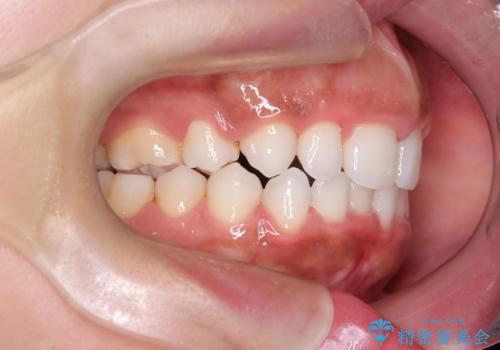

前歯の出っ張りとガタつきを改善

- 「前歯が出ていて並びも悪いのが気になる」との主訴で来院されました。診察の結果、上顎前歯の前突と中等度の叢生(ガタつき)が認められ、歯がきれいに並ぶスペースが不足していました。横顔のバランスと歯並びの両方を整えるため、上顎の左右の第一小臼歯2本を抜歯し、前歯を内側に下げながら歯列全体を整える治療計画を立てました。

患者さんのご希望もあり、取り外しが可能で目立ちにくいインビザライン(マウスピース矯正)を選択。抜歯スペースを活用しながら、叢生と前突感の改善を同時に目指しました。